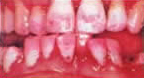

まずは左の写真を御覧ください。これはカテキンによる洗口試験を行う前の状態の口の中です。赤い部分は歯垢です。この口の中にはかなりの量の歯垢と歯周ポケットが存在しています。

そこでカテキンでを含む洗口剤によりどのような変化が見られるのか実験してみました。赤い部分が歯垢(プラーク)です。